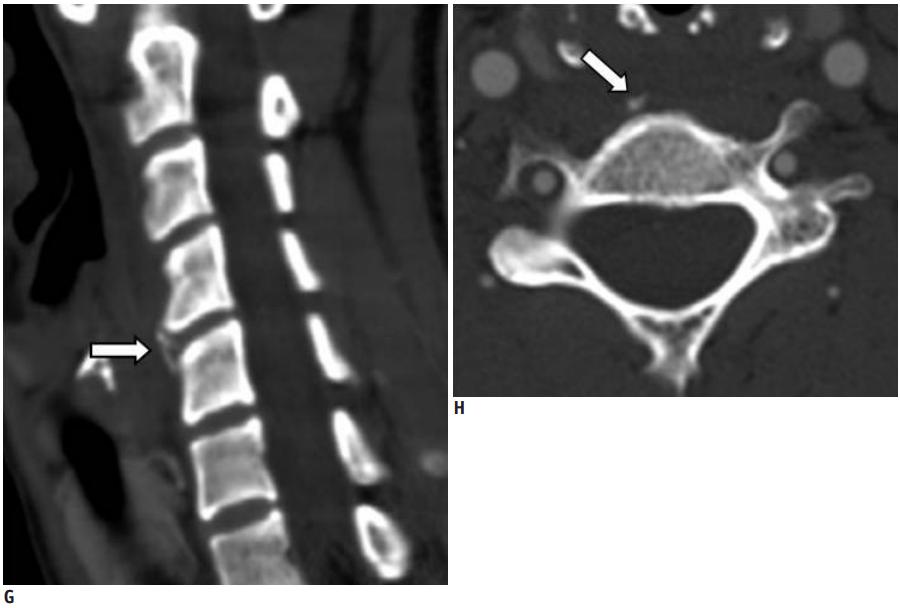

40岁男性,低热伴急性颈痛、张口困难1天,颈椎CT提示椎前钙化(箭头),经洛索洛芬60mg,每日三次,连续五天治疗,3天后症状改善,3月复查CT钙化消失。(PMID: 25918175)

32岁男性,颈肩部疼痛1月,喝水时轻度吞咽困难伴颈椎活动受限,无发热,化验指标正常,经非甾体抗炎药和秋水仙碱治疗后症状改善,4月后复查颈椎侧位片(D,E)钙化消失。(PMID: 25941110)

上述病人,E为增强,F为抑制像,G和H:经非甾体抗炎药治疗3天后查颈椎CT示C4-5椎前无定形钙化。